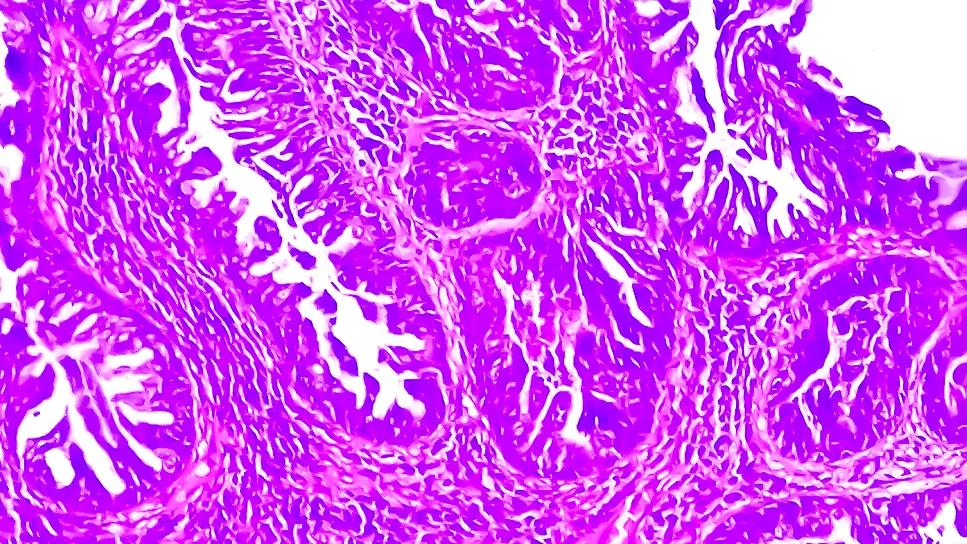

Squamous cell carcinoma

Lymphovascular invasion (LVI) is not part of the two most commonly used squamous cell carcinoma staging (cSCC) systems. However, this invasion of cancer to the blood vessels and/or lymphatics is an independent predictor of metastasis and disease-specific death, according to a major international study. The findings were published in the Journal of the American Academy of Dermatology.

CSCC usually is highly treatable with favorable outcomes, but in a small percentage of cases, patients who have high-risk features such as poorly differentiated histopathology, deep invasion or perineural invasion (PNI) do not fare as well. LVI is rare, so to date it’s been unclear what its full impact is on patient outcomes.

LVI can be elusive and difficult to identify on histopathology. Typically, Mohs surgeons check the edges of the excision of a cSCC tumor to confirm they’ve removed all abnormal cells, but LVI may be at the center of the tumor (i.e., the nonmarginal skin) and therefore may be missed using this approach.